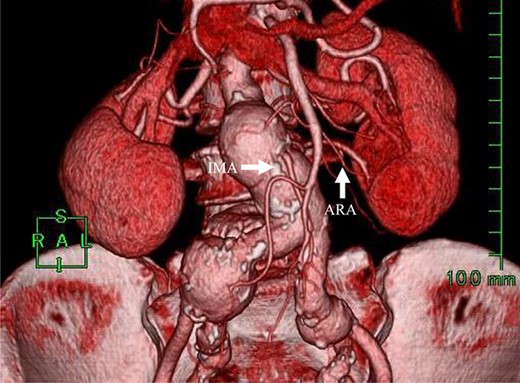

Angiography for decision-making revealed a type II endoleak from the IMA to the AAA, but no other visible endoleak (Fig. 2). Based on these findings, we planned additional EVAR for left CIAA, which was thought to have enlarged in natural course, and IMA embolization for the type II endoleak associated with sac enlargement. A staged strategy was devised. IMA embolization was planned several days after EVAR. Sac angiography from the IMA via Riolan’s arcade showed a flow-through endoleak to the ARA as a drainage artery (Fig. 3). Based on this finding, we embolized the ARA and the IMA with coils via Riolan’s arcade (Fig. 4). Selection and embolization of the drainage artery were technically feasible because of the flow from the IMA to the ARA. No deterioration of renal function due to ARA embolization was observed. One year after treatment, a CT scan demonstrated that the sac shrank to 42 mm with no evidence of a continuing endoleak (Fig. 5).

Sac angiography from the IMA via Riolan’s arcade showed a flow-through endoleak to the ARA as a drainage artery.